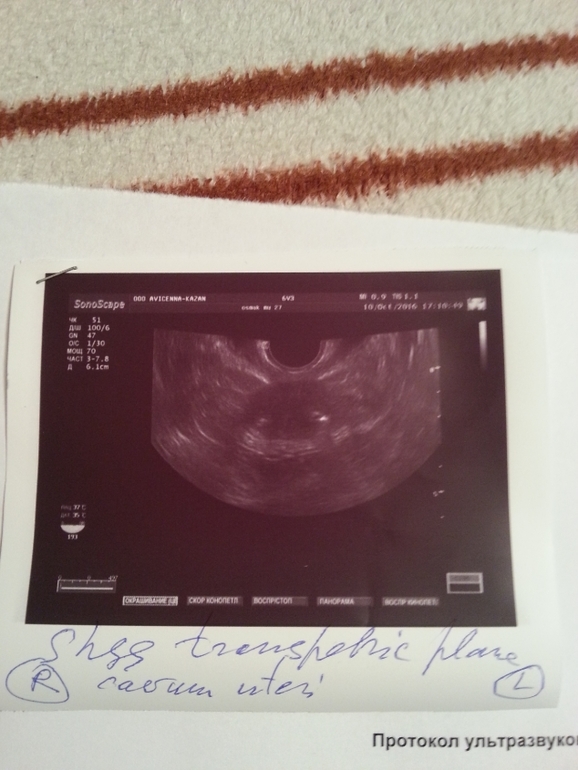

Девочки привет! Сделала сегодня гсг методом узи.Выкладываю фото результатов.Боли не было ни грамма.Ничего не чувствовала,только когда вводили жидкость немного распирало живот.Завтра побегу к врачу,но вы сами понимаете,это будет завтра! Хочу у Вас спросить,что делать с таким диагнозом? Узист сказал только эко.Но вот летом была бхб.И всё в голове перемешалось,переживаю очень. В ноябре собирались делать стимуляцию,а перед ней решили гсг(с врачом)сделать.И вот такой результат!(((